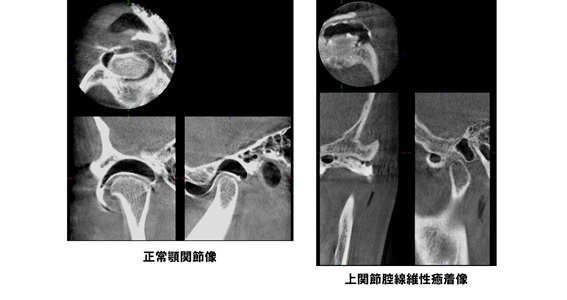

顎関節症は放置すると、初期の関節炎から、関節円盤の癒着・穿孔・転位、変形性関節症と病態が進んでいくことがわかってきました。

顎関節造影検査

検査所見